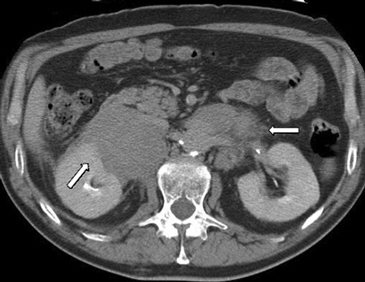

En la actualidad su uso es excepcional y su indicación esta reservada para casos en que las técnicas no invasivas no son diagnosticas y en casos en que se sospecha un linfoma y es necesario tipificarlo. En el lado derecho si la masa es pequeña se prefiere el abordaje transhepático (Figura 16 a) y en el lado izquierdo la vía dorsal posterior (Figura 16 b).

La vía transhepática sólo se realiza con aguja fina, de manera que si en el lado derecho es necesario obtener mayor cantidad de tejido, la biopsia se realiza con una aguja de tipo trucut pero el acceso tiene que ser por vía dorsal posterior.

A

B